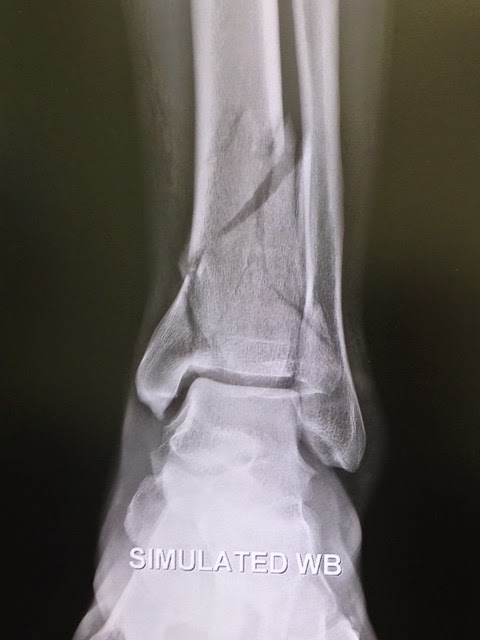

On February 10, 2013, I took an awkward fall while skiing and heard the crunch of multiple bones breaking in my leg. When I was taken to first-aid at the mountain and they removed my ski boot, the orthopedist on-site said he wasn't even going to bother taking an x-ray as it was clear that from how my foot was hanging and the multiple bones pushing against the skin that I would need surgery.

The next morning I was in Dr. Levine's office and the x-ray and MRI confirmed that I had indeed shattered my tibia into multiple pieces (x-ray and MRI attached). Surgery was scheduled for 3 days later on Valentine's Day 2013. The surgery lasted just shy of 6 hours as Dr. Levine pieced my leg together with multiple plates and a more than a dozen screws (post-surgery x-ray attached). The anesthesiologists (Drs. Michael Gordon, James Beckman, and Seth Waldman), Dr. Levine's PA, Lisa Pearson, and the entire staff were fabulous.